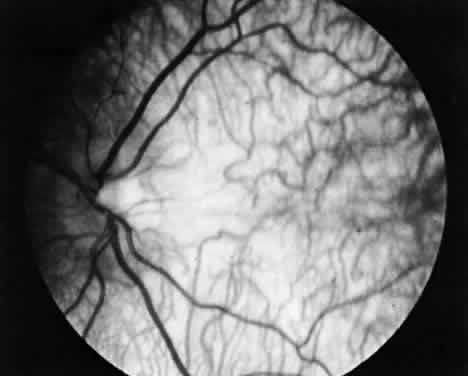

Albinism comprises a heterogeneous group of clinical syndromes exhibiting hypomelanosis based on heritable metabolic defects of the melanin pigment system. All types of albinism are characterized by foveal hypoplasia, nystagmus, photophobia, and decreased visual acuity in addition to absent or decreased melanotic pigment in skin, hair, and eyes (oculocutaneous albinism [OCA]) or in the eye alone (ocular albinism).31 The term albinoidism refers to hypomelanotic disorders in which the patients do not have nystagmus, decreased visual acuity, or foveal hypoplasia. Eleven disorders have been identified with clinical features of oculocutaneous albinism and four with features of ocular albinism (Table 4). The ocular findings in oculocutaneous albinism are listed in Table 5 (Figs. 2 and 3).

Fig. 3. Pigmentary dilution of the retina in oculocutaneous albinism. Note the absence of the macular reflex. Large and tortuous choroidal vessels are easily seen; these vessels are not visible when the retinal pigment epithelium is normal.